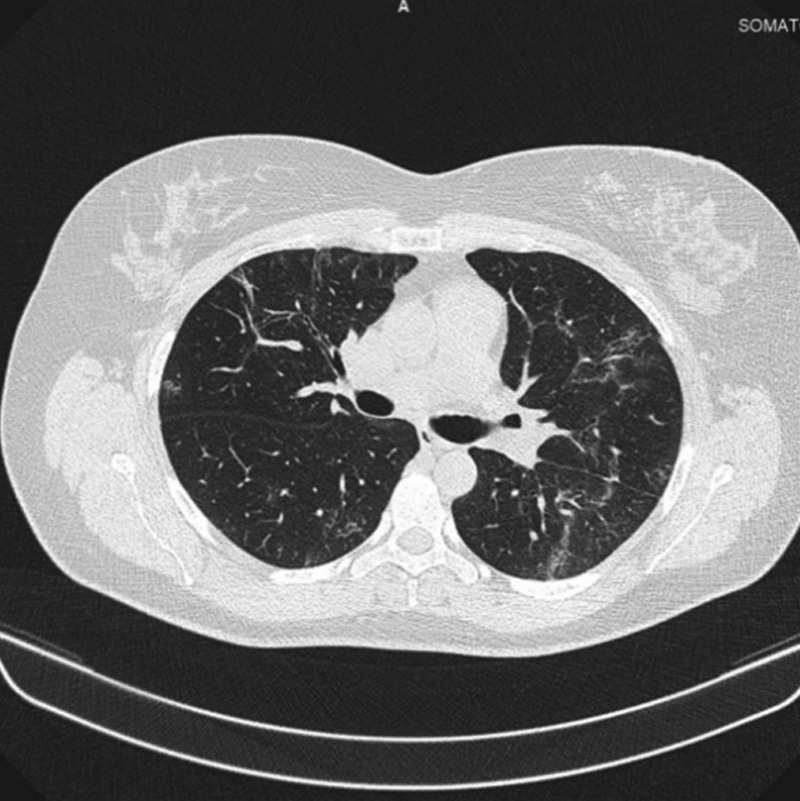

Через 4 мес. после выписки выполнено контрольное КТ ОГК: легкие без очаговых и инфильтративных изменений. С двух сторон определяются участки консолидации легочной ткани. На КТ признаков инфильтративных изменений легких не выявлено, явления пневмофиброза отсутствуют, КТ-картина перенесенной вирусной пневмонии.

Рис. 2. Компьютерная томограмма органов грудной клетки после завершения курсового лечения препаратом бовгиалуронидаза азоксимер

Fig. 2. Computed tomography of the chest after the completion a course of Longidaza